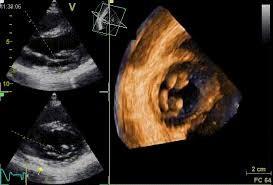

-Ecocardiograma: hipertrofia concéntrica grave del ventrículo izquierdo con fracción de eyección del ventrículo izquierdo conservada.